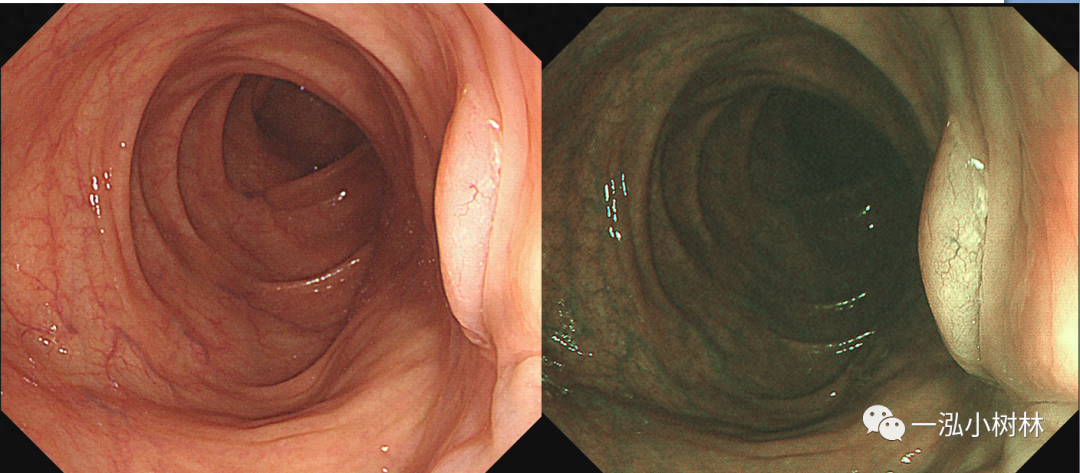

图4 结肠管状腺瘤(Pit Pattern IIIS+IIIL型)

图5 结肠增生性息肉 (Pit Pattern II型)